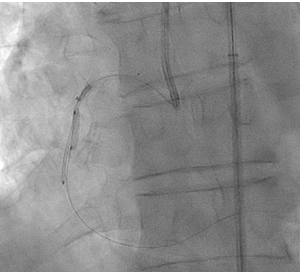

In view of this complication and the clinical instability of the patient, extraction of the device with a coronary snare was attempted but was unsuccessful (Figure 3). The access route was then changed to the femoral artery using an Amplatz left 6F catheter, and a Sion guidewire was advanced to the distal segment of the right coronary artery with the support of a 135-cm FineCross microcatheter (Terumo). This was followed by dilatation using a Sapphire II PRO balloon (OrbusNeich) (Figure 4) with catheter extension and anchoring of the balloon until 2 new everolimus-eluting stents (2.5 x 40 mm and 3.0 x 15 mm) could be advanced (Figure 5). Upon post-dilation of the noncompliant balloon, the previous stent and ballon were successfully crushed, obtaining a good final angiographic result (Figure 6). The procedure was completed with intracoronary optical coherence tomography, which confirmed adequate stent expansion and apposition, as well as the crushing of both the stent and the previous balloon (Figures 7-11).